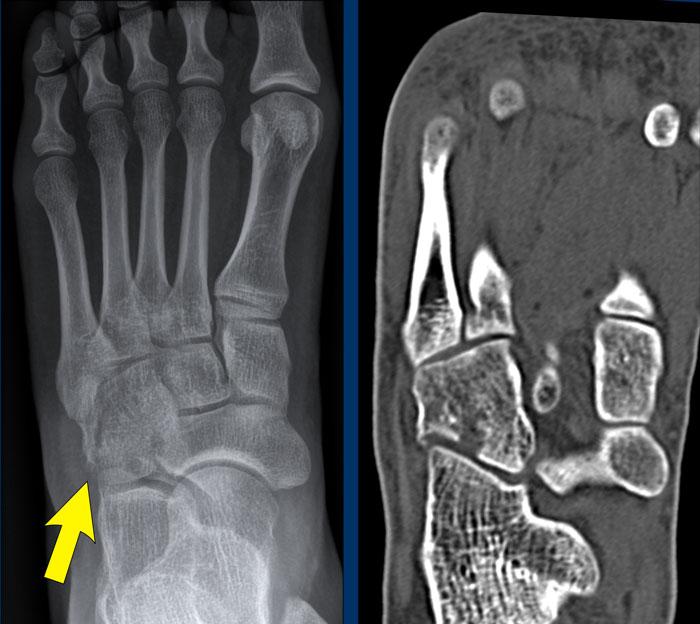

case 1 – distortion

The findings are:

- Khoảng cách lớn giữa nền xương bàn chân 1 và xương bàn chân 2 (mũi tên vàng).

- Bán trật khớp giữa xương hộp và nền xương đốt bàn chân thứ 5 (mũi tên trắng).

This means that there is a Lis Franck dislocation fracture.

CT xác nhận nhiều gãy xương ở mức độ các khớp cổ bàn chân (khớp Lisfranc).

Phức hợp dây chằng Lisfranc chạy giữa xương chêm trong (C1) và nền xương bàn chân thứ 2 và thứ 3.

It consists of 3 components:

- a dorsal ligament

- interosseous ligament

- dây chằng gan chân, có các điểm bám vào nền xương bàn chân 2 và xương bàn chân 3.

Nền của các xương đốt bàn chân tạo thành hình vòm giúp ổn định phần giữa bàn chân.

Giống như các vòm cửa sổ cổ, cần có một viên đá khóa vòm ở đỉnh để khép kín vòm lại.

Nếu viên đá này bị lấy đi, toàn bộ vòm sẽ sụp đổ.

Ở bàn chân, nền xương đốt bàn chân thứ 2 là viên đá khóa của vòm bàn chân.

Nếu nó mất kết nối với các xương đốt bàn chân khác, vòm bàn chân sẽ sụp đổ.

Điều này cũng sẽ dẫn đến nhiều vết bong gân của các dây chằng nối các nền xương đốt bàn chân với nhau.